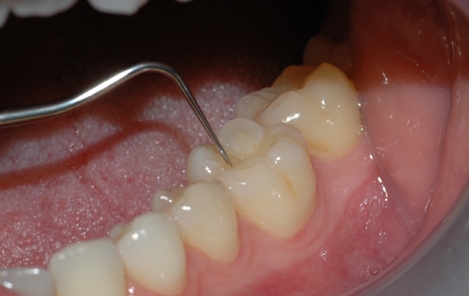

Tannstensfjerning, puss og poléring

Etter undersøkelsen er det vanlig at tannlegen eller tannpleieren fjerner tannstein og misfarging fra tennene. Tannstein består for det meste av kalkstoffer fra spyttet som avleires og legger seg på tannflaten som et hardt belegg. Det sitter så godt fast at det er nærmest umulig å fjerne på egen hånd med tannbørsten.

Tannlegen eller tannpleieren kan fjerne både tannstein og overfladiske misfarginger ved å rense, pusse og polere tennene. Tannsteinen fjernes enten med maskin eller ved å skrape den bort med håndinstrumenter. Misfarginger kan poleres bort med en spesiell pussepasta som inneholder ekstra slipemiddel. Alternativt går det an å benytte saltblåsing for å fjerne misfargingene.